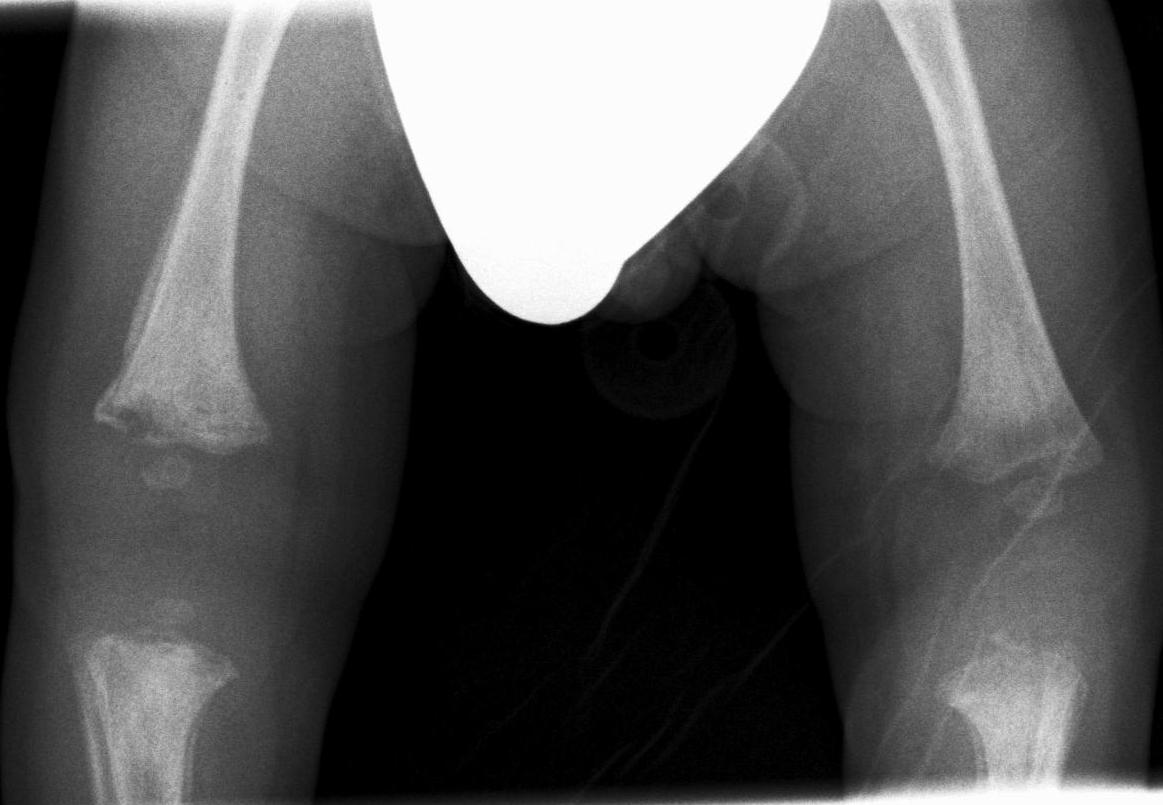

Battered child, child abuse, shaken baby syndrome, non-accidental injury. These are all synonyms describing the syndrome of child abuse (usually of newborns and infants). At many times only the radiologist can identify these cases. There are some characteristic injuries that are not in relation with the story the parents tell. Fractures of multiple numbers, or in various healing stages are indicative of child abuse. Complex skull fractures are rare in simple cases of falling. The most characteristic sings are metaphyseal or corner fractures on the metaphises of the tubular bones.

Violent shaking causes rib fractures and the to-and fro motion of the head leads to subdural hematomas, hypoxi-edematous contusion. X-ray examination: chest, bidirectional skull, vertebral and limb radiographs are necessary. US examination: both cranial and abdominal US are performed in infants. CT-examination can be required if the abdominal or the vertebral injuries are severe. MRI is unavoidable if neurologic symptoms persist.

Image

43. Comparison Radiograph of the knees. On the distal-lateral epiphysis of the right femur “corner” fracture is seen, lytic area, periosteal reaction. Both proximal tibia, on the visible part of the picture show periosteal reaction. Battered child.